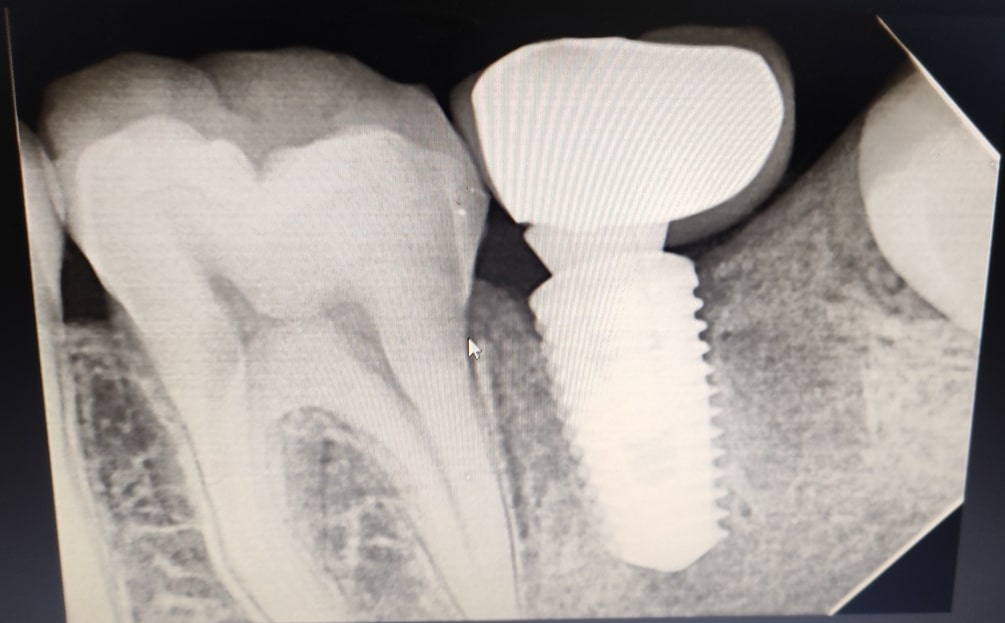

Dental Implants

Dental implants are long-term investment in oral health. Unlike other tooth replacement options, such as dentures or bridges, dental implants can last a lifetime with proper care and maintenance. They do not require any special cleaning or adhesives, and they do not put strain on adjacent teeth like bridges can.